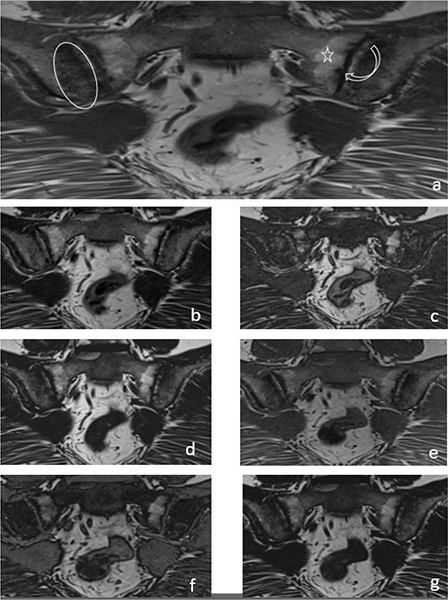

In the evaluation of chronic sacroiliitis, there was no significant difference in the detection of PFD (P = 0.08) (Figure 2) or ankylosis (P = 0.42) (Figure 3) among standard T1W, T1W–T2W Dixon (FO, IP and OP) images.

Figure 2

A 33‑year‑old female patient with iliac side sclerosis (ovoid circle), sacral side periarticular fat deposits (star) and iliac‑sacral facial erosions (curved arrow) in both sacroiliac joints marked on a T1W images (a). These findings can also be seen in T2W Dixon IP (b), T2W Dixon OP (c), T2W Dixon FO (d), T1W Dixon IP (e), T1W Dixon OP (f) and T1W Dixon FO (g) images.

It was observed that T1W–T2W Dixon OP images were insufficient to show the presence of erosion, but T1W–T2W Dixon FO and IP images were similar to those of the standard protocol (Figure 2).

T1W–T2W Dixon FO, IP and OP images were found to be inadequate compared with those of the standard protocol for revealing the presence of subchondral sclerosis (Figure 2). T1W Dixon OP images were found to be insufficient to show backfill (P = 0.016), and other Dixon images were found to be similar to the standard protocol (Figure 4).